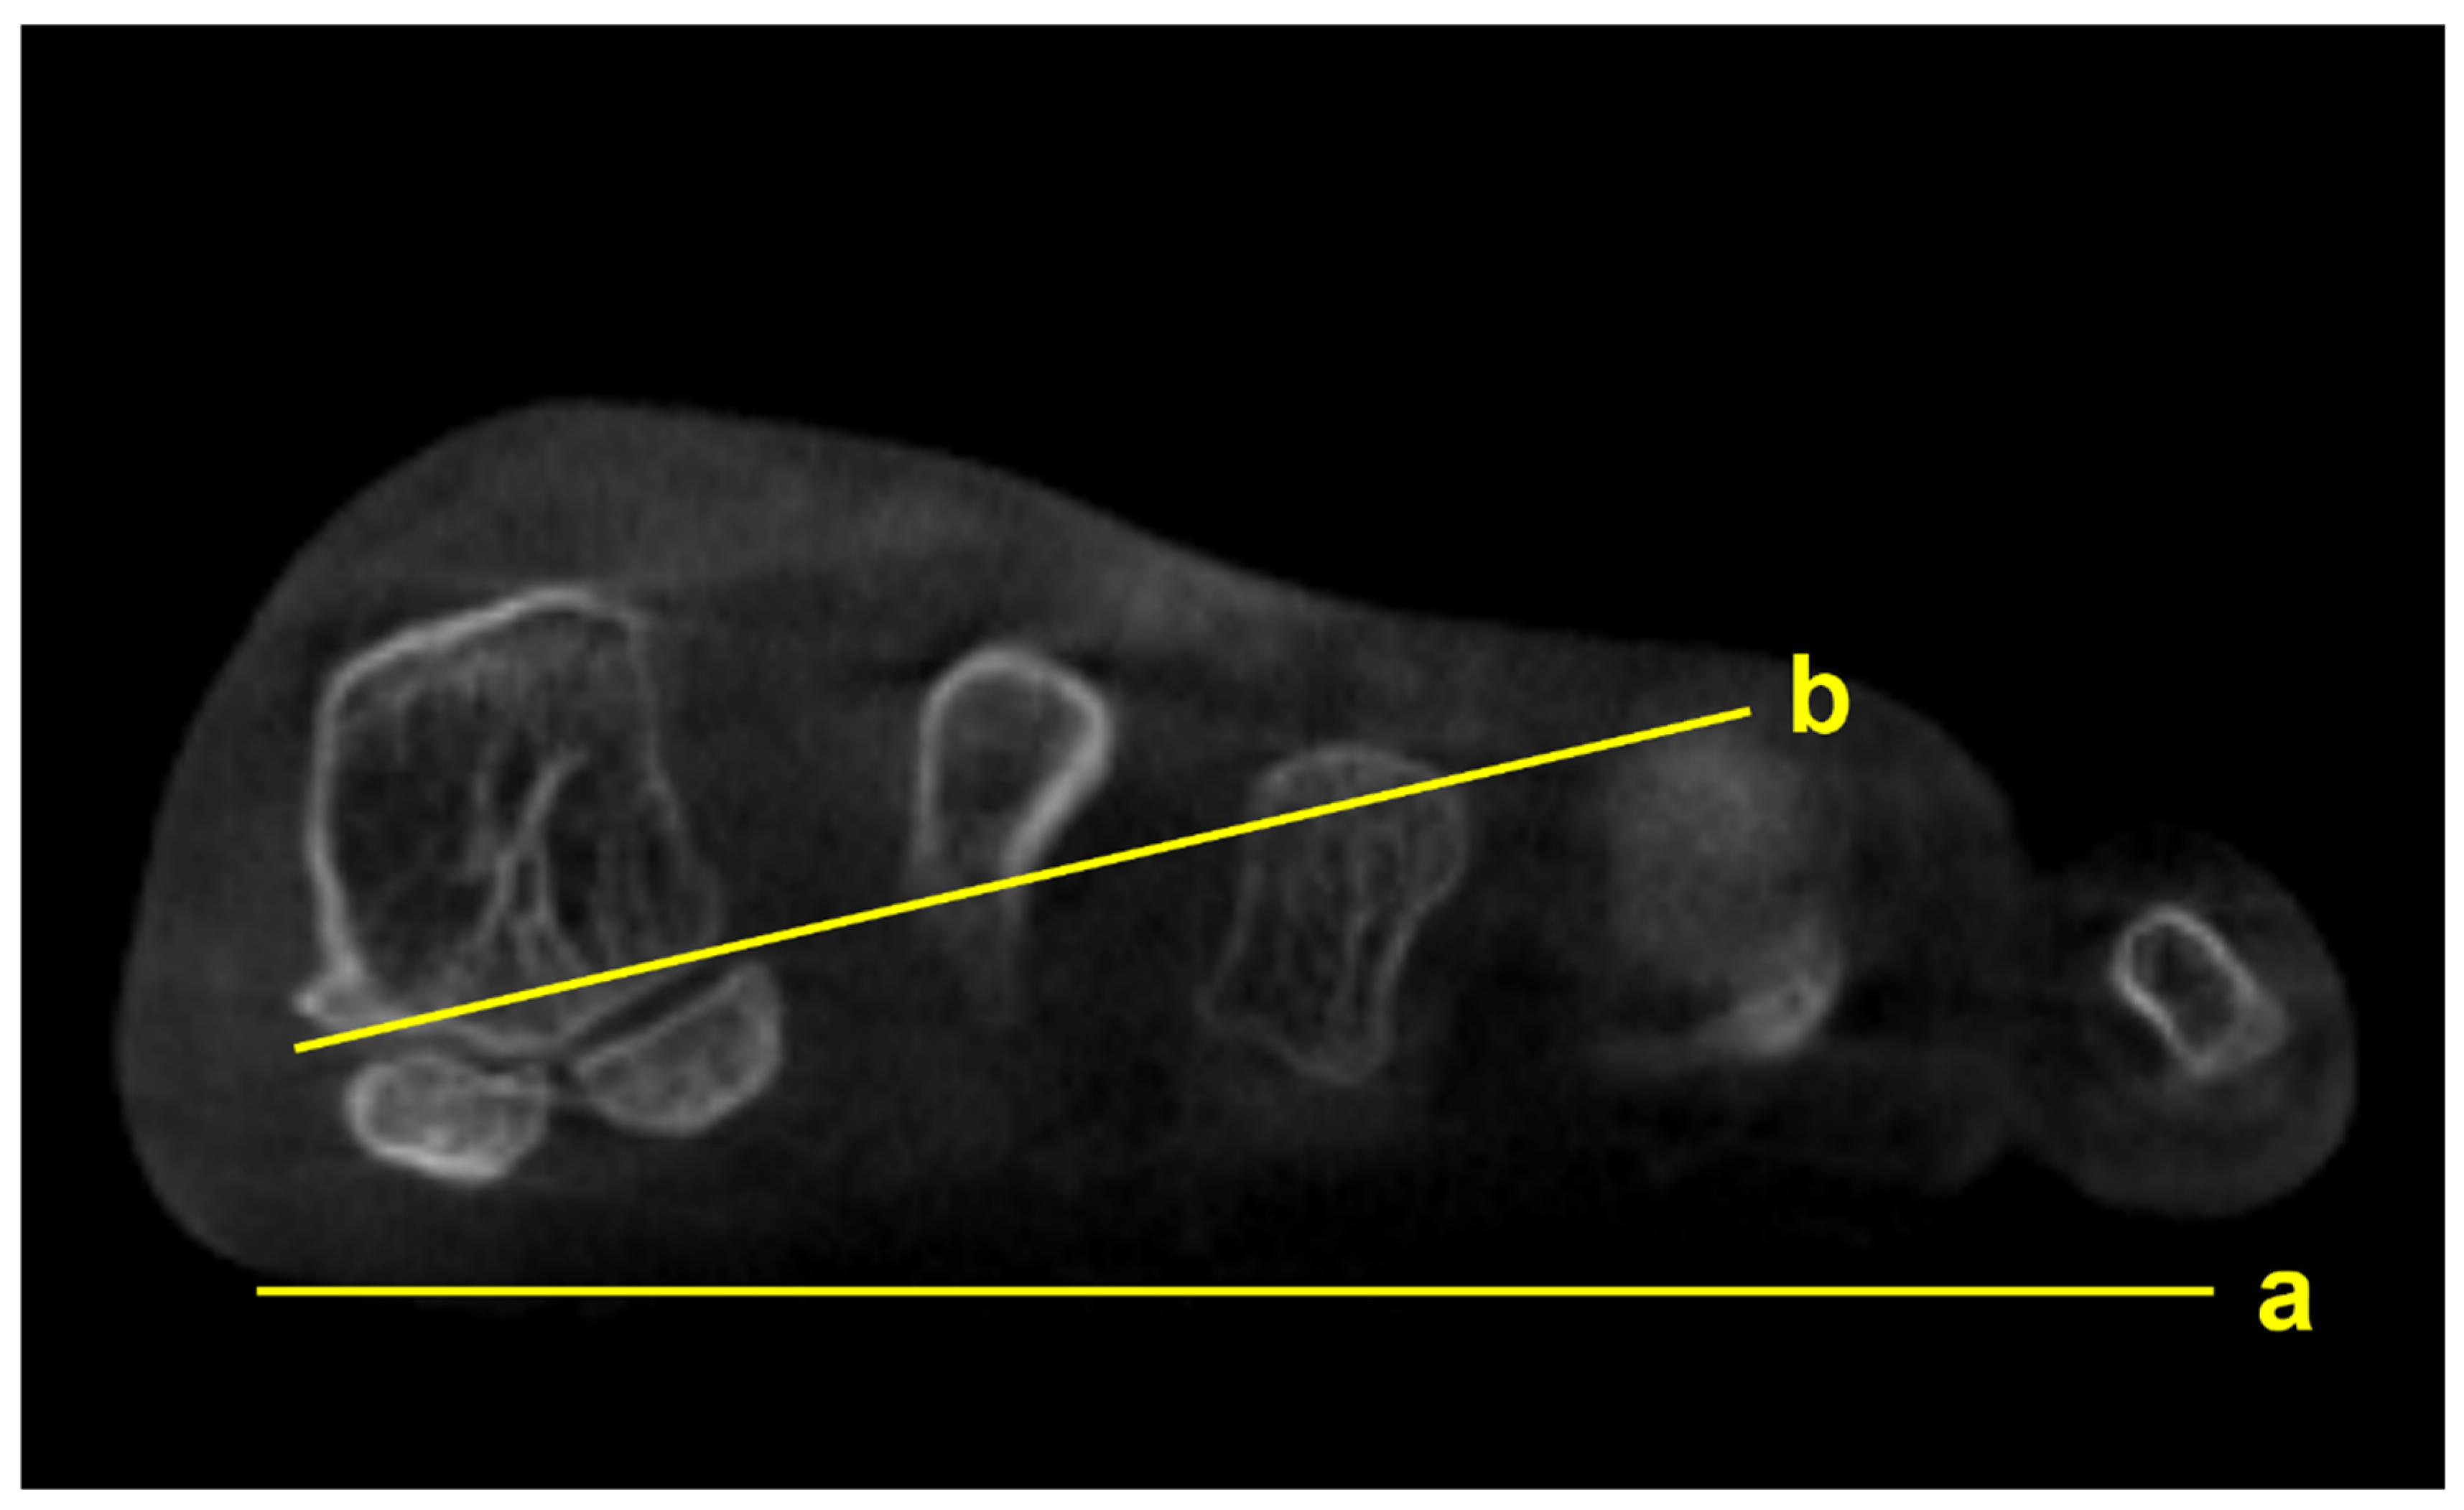

Several studies focused on the impact of M1 pronation after hallux surgery. Conti et al conducted a study to determine if postoperative decrease in M1 pronation observed in WBCT would be associated with changes in patient-reported outcomes [14]. Patients who underwent modified Lapidus procedure for hallux valgus were divided into two groups with regards to the amount of postoperative M1 pronation change, and the Patient Reported Outcomes Measurement Information System (PROMIS) scores were compared between groups. At 2 years postoperatively, patients who had significant decrease in M1 pronation after modified Lapidus procedure showed greater improvement in the PROMIS physical function domain. Choi et al utilized simulated weight bearing CT to evaluate the association between preoperative M1 pronation and postoperative recurrence after proximal chevron osteotomy [15]. To quantify the amount of preoperative M1 pronation, authors measured M1 pronation angle (M1PA) (Figure 3). They reported that patients who had significant correction loss at 1 year after surgery exhibited higher preoperative M1PA, with a 28.4 degrees threshold. These results pose an importance of recognizing preoperative M1 pronation through WBCT because rotational component of the hallux valgus deformity would impact postoperative outcomes and recurrence rates after surgery.

Figure 3. M1 pronation angle (M1PA) is the angle between the floor (a) and a line drawn from the most inferomedial border of the medial sesamoid facet to the most lateral border of the lateral sesamoid facet (b).